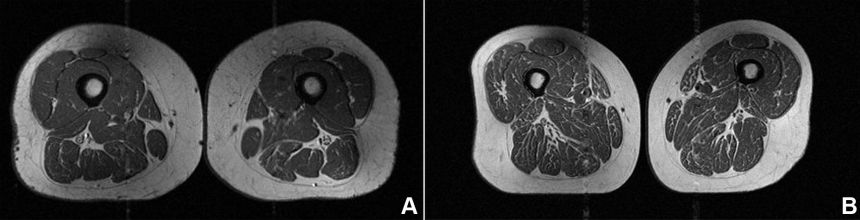

In a new study published in the journal Radiology, researchers pored over MRI scans from 615 adults enrolled in the Osteoarthritis Initiative, a long-term project tracking knee health. None showed signs of osteoarthritis at the scan time, yet those with diets richest in ultra-processed foods had the most fat woven into their thigh muscles, regardless of calorie intake or BMI.

Lead author Dr Zehra Akkaya, from the University of California, San Francisco, spotlighted one extreme case. A 62-year-old woman’s thigh resembled premium beef after deriving 87 per cent of her calories from items like sugary cereals, chocolate bars, and fizzy drinks. “This participant’s diet was mainly comprised of cold cereals, chocolate candy or candy bars, regular soft drinks or bottled sugary drinks,” she explained.

“It was especially concerning because these individuals, scanned at a time when they had no signs of knee osteoarthritis, already showed compromised muscle quality,” Akkaya added. These foods, which make up more than half of U.S. adults’ calories (and 62 per cent for children), tie into obesity, cancer, heart disease, diabetes and depression.

“Throughout the study, the more ultraprocessed foods a person consumed, the more intramuscular fat they had in their thigh muscles, regardless of caloric intake,” said senior author Dr Thomas Link. While causation needs more proof, the wake-up call is clear: cut back to protect your muscles and joints.